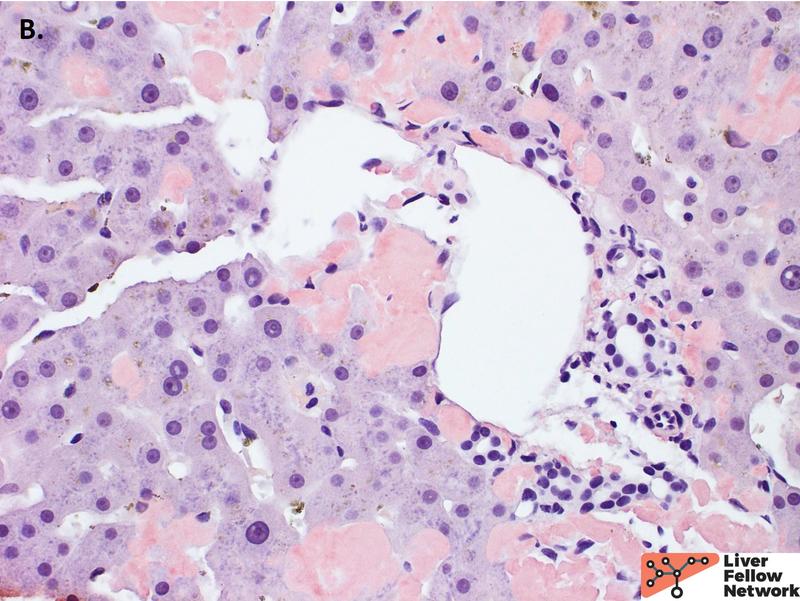

On higher power, the amorphous material distends the sinusoids causing atrophy of the hepatocellular plates (Figure 2A), with patchy involvement of the portal tracts (Figure 2B). Masson trichrome was evaluated for evidence of fibrosis. The amorphous material stains a paler blue on Masson trichrome compared to true collagen deposition/fibrosis (Figure 3). Congo Red stain was performed to further evaluate the deposits, which shows red-orange positive staining under non-polarized light (Figure 4A and 4B). With polarization, the deposits show “apple green” birefringence, confirming the presence of amyloid within the liver (Figure 4C and 4D).

As with other sites within the body, amyloid deposition in the liver presents as acellular eosinophilic amorphous material. It can be found within the sinusoids and/or vessel walls. Sinusoidal deposition can compress the hepatocytes leading to hepatocellular atrophy and can efface the overall architecture. Macrophages and multinucleated giant cells may also be seen surrounding amyloid deposits. Congo red special stain performed on 10 μm thick sections is gold standard for diagnosis. Amyloid will show red-orange positive staining under non-polarized light. Under polarized light, best viewed in a darkened room, a positive Congo red stain will demonstrate the characteristic “apple green” birefringence. Falsely negative Congo red can be due to technical issues such as performing the stain on the incorrect thickness of the section. Falsely negative birefringence can be due to user-related issues such as insufficient brightness of the microscope light source or too much ambient light.